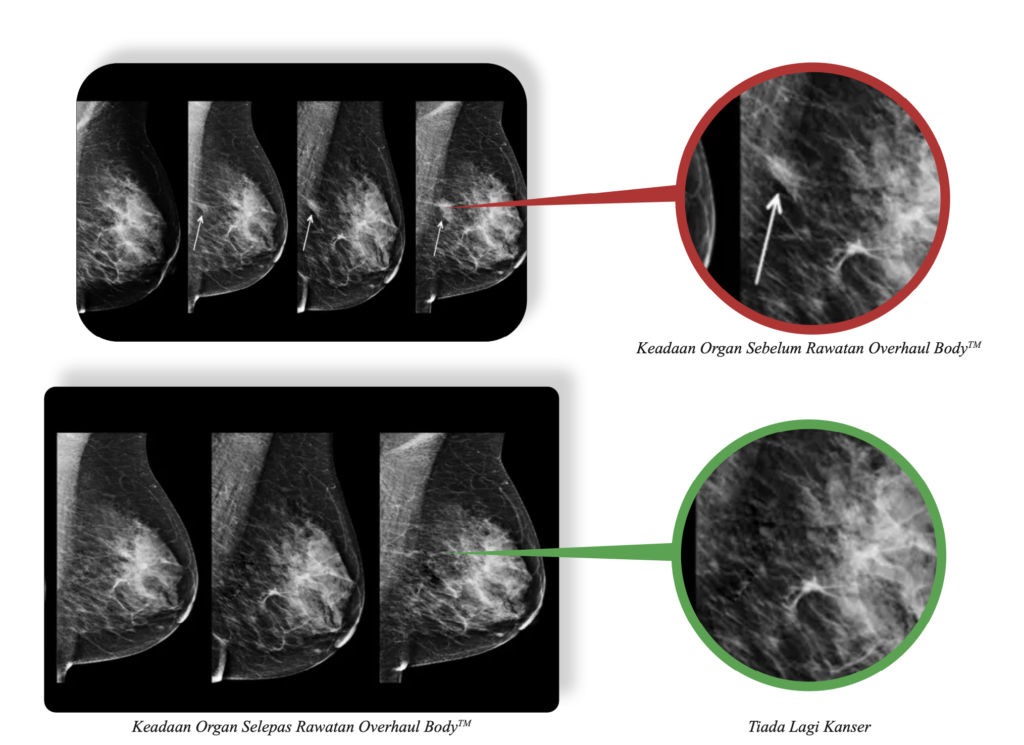

Sebelum ini, saya menghadapi cabaran kesihatan tahap 3 yang serius melibatkan kesejahteraan dalaman dan payudara selepas menemui ketumbuhan 3.5 cm. Keadaan yang kompleks ini menjejaskan sistem limfatik, hati, dan reproduktif saya. Walaupun rawatan hospital membantu mengurangkan gejala awal, kesan sampingannya seperti keletihan melampau dan ulser mulut sangat mencabar buat saya.

Selepas melengkapkan rawatan utama, saya merasakan badan memerlukan jalan lebih holistik untuk mengembalikan kekuatan. Saya memilih program kesejahteraan di Ibnu Sina Wellness™ bagi menyokong proses pemulihan saya.

Hasilnya sangat mendalam; badan memberikan tindak balas luar biasa sehingga ketumbuhan fizikal dan kerisauan dalaman kini tidak lagi dikesan tanpa sebarang tanda isu berulang. Tenaga saya telah kembali; saya kini boleh bersenam dan mendaki, kulit lebih sihat, malah dapat menyempurnakan puasa Ramadan sepenuhnya.